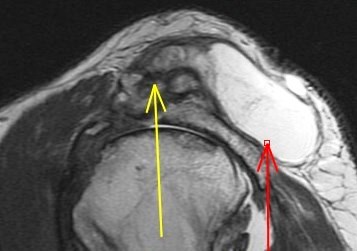

82 y/o with shoulder mass

Large cyst arising from the AC joint in the setting of a chronic rotator cuff tear. Reference article.

Geyser phenomenon